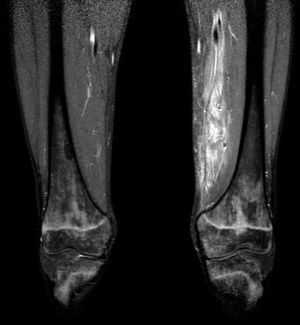

After three days of treatment, the patient persisted with the same symptoms showing no improvement. A soft tissue ultrasound reveled a dysfunctional muscle area in relation with the vastus medialis of quadriceps and the adductors muscles compatible with pyomyositis (Fig. 1). A MRI study confirmed the diagnosis (Fig. 2). Consequently, our department was consulted in order to consider surgical debridement. Finally he was taken to surgery performing a complete debridement and drainage of the muscle injury. Samples were collected and sent for microbiological study, identifying an infection due to E. coli as the causative agent.